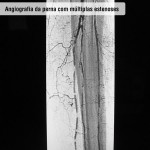

Diagnóstico

O exame clínico é suficiente para diagnosticar a doença, mas, para garantir com precisão o grau da obstrução, utilizam-se a ecografia Doppler e a arteriografia.

Doença obstrutiva em diabéticos